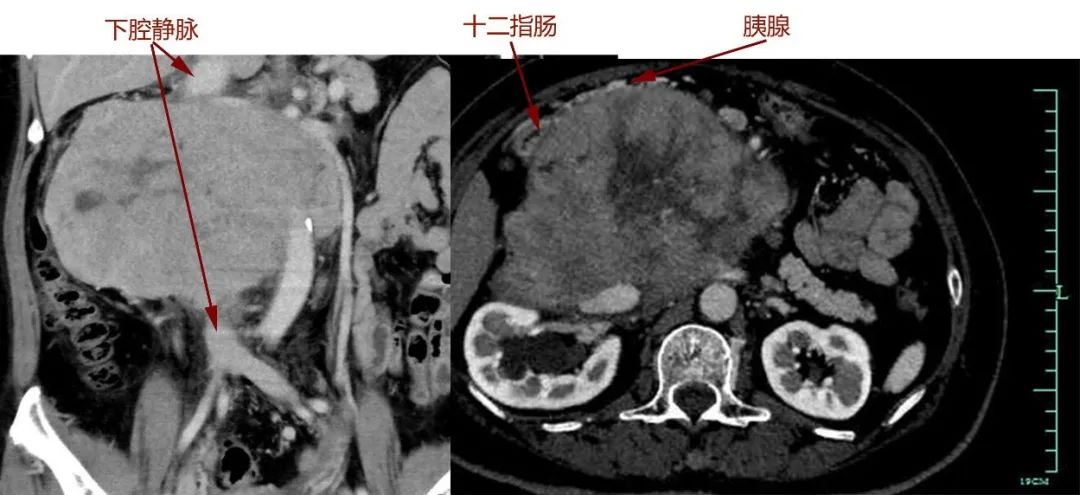

前段时间,吴女士偶尔觉得上腹部闷胀不适,本来以为是胃病,但配了胃药后症状丝毫没有缓解。随后,她感觉吃饭都受到影响了,胃口越来越小,从来没有过这种情况的吴女士,赶紧来到浙大一院安吉分院就诊,不想检查结果不仅让全家人恐惧,就连接诊的医生也皱起了眉——吴女士后腹膜区长了一个超20厘米的巨大肿瘤,将近有一个足球大小,压迫重要脏器和直连心脏的下腔静脉,复杂凶险的病情让当地医生犯了难。

很快,吴女士转院至浙大一院肿瘤外科,完善各项术前检查后,滕教授发现情况远比最初判断严重:肿瘤与胰十二指肠、肾脏等多个脏器及主干血管关系不清,直接吞噬了腔静脉,双肾血管受累,已有轻度肾功能异常。

手术过程和预计的一样凶险,手术团队小心翼翼将肠道、肾脏血管从肿瘤成功分离。但真正的困难很快出现:肿瘤与胰腺头部黏连,下腔静脉也被侵犯,滕教授当机立断,切断十二指肠及胰头,游离肿瘤两端下腔静脉,最后分离切除大血管部分肿瘤。由于肿瘤向血管内生长,肿瘤切下的同时血液一涌而出,早有准备的团队立即阻断下腔静脉以控制出血,快速切除肿瘤,张鸿坤主任随即缝合修补下腔静脉。万幸的是,术中发现肿瘤与肠系膜血管黏连不严重,避免了自体小肠移植。